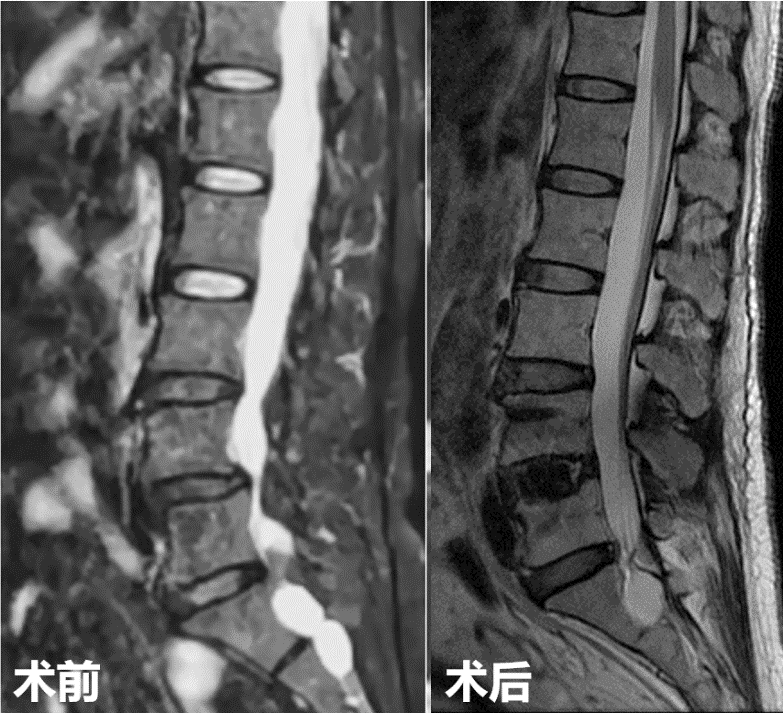

第一例患者女性,73岁,因“腰部反复疼痛20余年,加重伴左下肢疼痛4月”以“腰椎滑脱症(L3、 I°)、腰椎管狭窄症”住院。入院后经术前讨论、评估后制定治疗方案,并与患者及其家属充分沟通,行OLIF手术。术后第二天,患者下地活动,腰痛和左下肢疼痛完全消失,无明显不适,疗效满意。

第二例患者男性,67岁,患者因“腰痛并右下肢放射痛1年余,加重1月”入院,发病以来反复保守治疗,未好转,1月前症状加重,间歇性跛行,行走100米后因疼痛无法继续行走。入院后经术前讨论、评估,制定治疗方案,行OLIF手术。次日患者下地活动,下肢症状消失,疗效满意。

术前影像

术中

术后复查